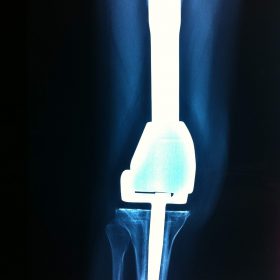

Παρόλα αυτά στην πλειονότητα των περιπτώσεων, με την πάροδο του χρόνου οι παραπάνω τρόποι αντιμετώπισης καθίστανται αναποτελεσματικοί. Η ένταση του πόνου και ο αντίκτυπος στην καθημερινότητα γίνονται αφόρητα.

Σε αυτό το σημείο η Αρθροπλαστική Γονάτου αποτελεί μονόδρομο.